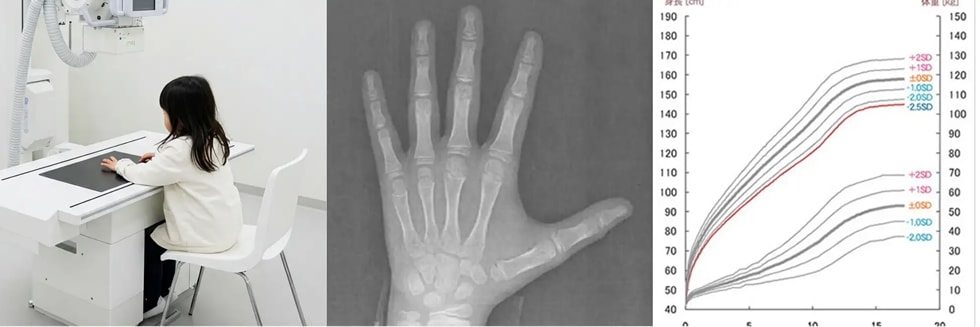

「あと+5cm」を叶えるための成長ホルモン治療。当院の身長予測シミュレーションは「現在のお子様の身長」や「ご両親の身長」といった基本的な情報に加え、レントゲンを用いた骨年齢の測定による、より精度の高い精密な身長予測が可能です。これらの情報をもとに、お子様の最終的な身長を予測し、医師より治療方針について丁寧にご説明いたします。

左から、レントゲン撮影の様子(イメージ写真)、レントゲン画像、身長予測シミュレーション